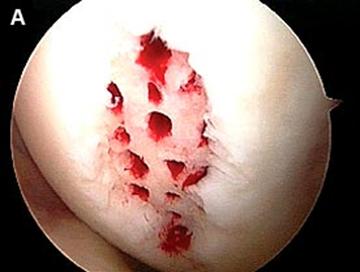

Debridarea (a, b, c).

a. b.

Fig.25.a. Debridarea. Fig.25.b. Microfracturare.